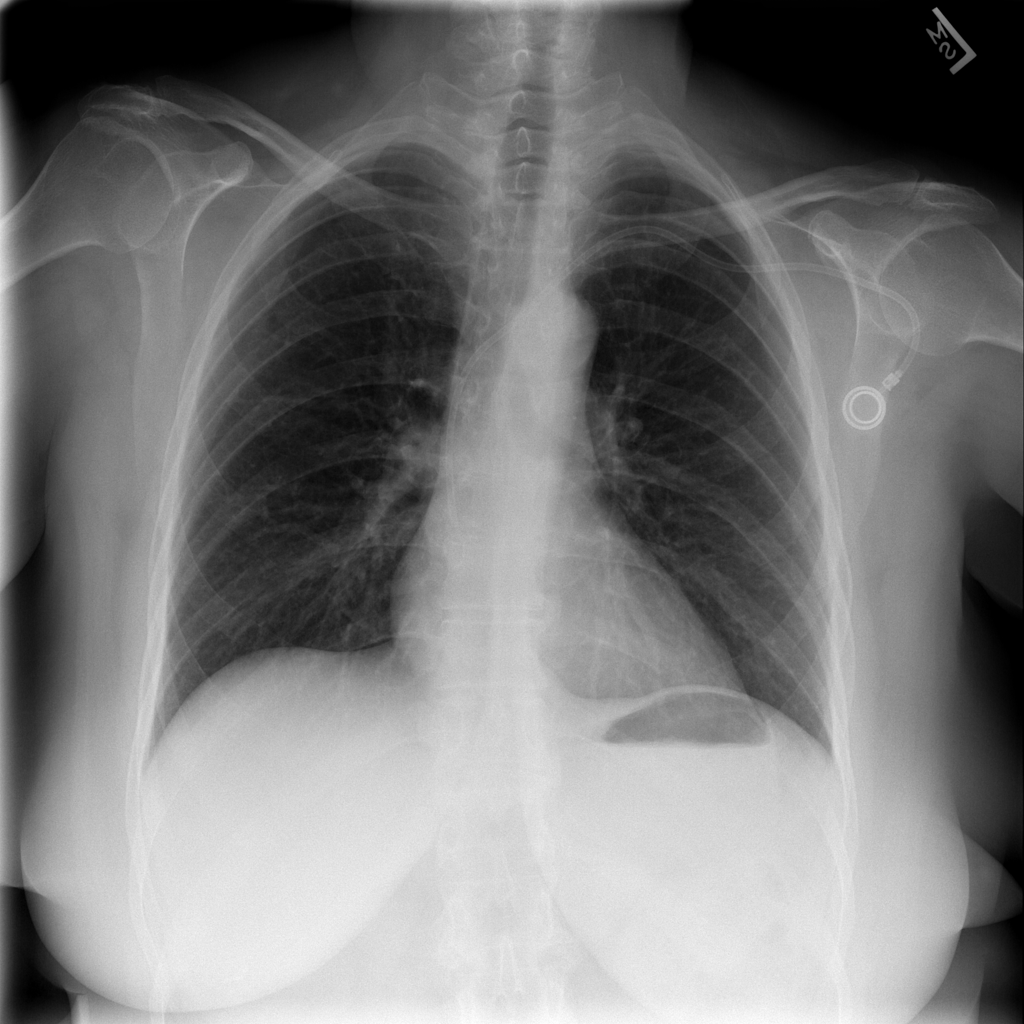

Showing up to 90 reference images for Hernia.

PAT-4F7E · IMG-000Hernia

PAT-4F7E · IMG-000

PA